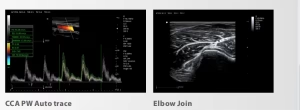

| Modos de imagen | B, Dual-B, Quad-B, M, B+M, 2CFM (Color Flow), PW (Pulsed Wave), CW (Continuous Wave), PDi, THI |

Diagnóstico avanzado y versátil: gracias a sus modos 2D, Doppler color, PW y CW, el CU45 permite una amplia gama de estudios en cardiología, ginecología, abdominal, vascular y veterinaria.